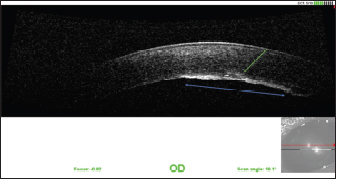

The various follow-up visits revealed improvement in comfort, with the disappearance of the blepharospasm. The corneal edema was greatly improved. The visual tests were positive and the intra ocular pressure (IOP) was stable. Six months after the surgery, the observable sequelae were the persistence of discrete corneal edema in the area of the point of penetration of the claw as well as dyscoria (Fig. 6). The tear area of the endothelium and Descemet membrane was still visible at high magnification (Fig. 7). One year after the surgery, the vision tests were positive. The cornea had fibrosis at the point of impact and opposite the endothelium and Descemet membrane tear, which was still visible (Fig. 8). The pupil was slightly deformed and the capsule of the lens was partially fibrosed. Optical coherence tomography (OCT) of the cornea revealed fibrous metaplasia of the endothelium and probable duplication of the Descemet membrane. The intraocular pressure was measured to be 13 mmHg by rebound tonometry (Fig. 9).

Fig. 9. OCT of the cornea 1 year after the surgery. Note the fibrous metaplasia of the endothelium (blue arrow) and probable duplication of the Descemet membrane (green arrow).